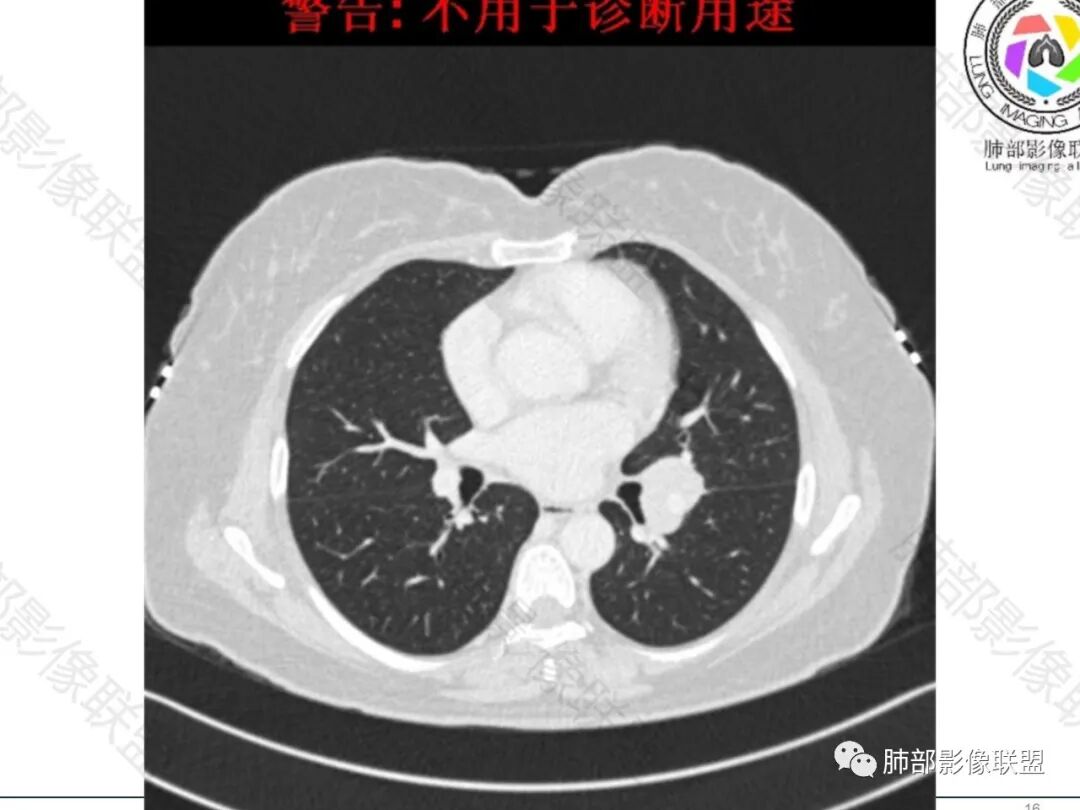

左肺门增大,可见一实性结节,病变跨叶裂生长,边缘平直,膨隆,平扫密度均匀,增强后可见均匀强化,病变包绕血管束,血管走行自然,纵隔淋巴结肿大,右乳腺似有一小结节?临床:女性47岁,无感染症状,考虑:淋巴瘤,小细胞肺癌,结核(坏死不明显),结节病(单侧少见)

中年女性患者,轻咳月余,胸部CT:左肺门肿块,边缘光滑,内部密度均匀,包绕支气管及肺动脉。纵隔淋巴结增多,部分增大。考虑恶性SCLC可能。

左肺门占位,包绕支气管血管,支气管狭窄未见堵塞,考虑淋巴瘤

中年女性,临床症状不明显,左肺门肿块影,边缘清晰,可见分叶,包绕支气管生长,右侧肺门可见增大淋巴结,增强病灶强化不明显,可见血管漂浮征,考虑肿瘤性病变,淋巴瘤,小细胞癌,神经内分泌癌。

女性,47岁,轻咳月余。CT示:左肺门不规则病灶,包绕气管血管生长,增强扫描轻度强化,纵隔可见略大淋巴结,临近支气管受压狭窄。综合考虑为恶性,淋巴瘤或小细胞肺癌可能

左肺门肿块,边界清晰,跨叶间裂生长,病灶整体感觉偏软,包绕血管及支气管,增强后轻度均匀强化,无坏死,考虑淋巴瘤可能大

流心明智:

女,47,轻咳月余,偶感乏力。胸部CT:左肺门肿块,跨叶裂,边缘膨隆,平扫密度均匀,增强后可见均匀强化,病变包绕血管,血管走行自然,纵隔多发淋巴结肿大(2R、3A、4R、4L、5、6、L10-13),右乳腺有一小结节。考虑:淋巴瘤>小细胞>转移>TB>结节病。

女性,47岁,轻咳月余,偶感乏力。CT示:左肺门不规则病灶,包绕气管血管生长,血管漂浮,临近支气管稍受压狭窄;增强扫描病灶轻度强化,纵隔可见多个略大淋巴结,综合考虑为淋巴瘤可能,小细胞肺癌待除。